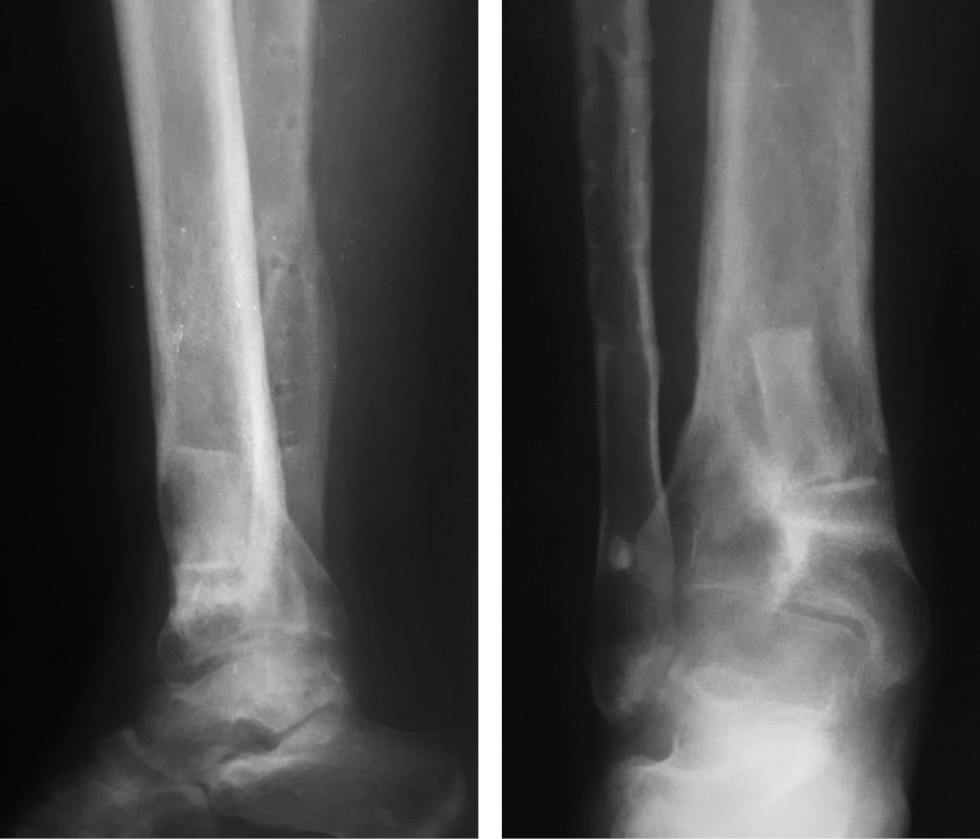

An 11-year-old patient, who had catatrauma, sustained a closed comminuted fracture of the distal metaepiphyzes of the bones of both legs (AO type 43C2.1), with compartment syndrome and compression fracture of the L4 vertebral body (type A1). She underwent surgery in a regional center, and external fixation devices (EFDs) were installed for both feet and fasciotomy on both lower legs. Within 2 weeks, focal soft tissue necrosis developed in the lower third of the inner surface of the right leg, and necrectomy, vacuum-assisted closure therapy, and dressings were performed. Over time, a fistula with purulent discharge had formed. One month later, the EFD was remounted, with open reduction, and extracortical osteosynthesis of fragments of the fibula was performed. Three months after the injury, the EFD was dismantled, and the patient received outpatient follow-up and treatment (dressings and repeated courses of antibacterial therapy) by a traumatologist at the primary healthcare facility; however, fistulation was persistent. One year after the injury, the patient was rehospitalized to a regional clinic for a diagnosis of chronic post-traumatic osteomyelitis of the distal metadiaphysis of the right tibia. Status localis included pain in the ankle joint, presence of a fistula, and X-ray signs of chronic osteomyelitis of the distal metadiaphysis of the tibia. According to the documentation, the patient underwent sequester necrectomy of the lower third of the right tibia. Two weeks after the surgery, clinical signs of inflammatory activity persisted (seropurulent discharge and fistula).

She was admitted to the clinic 1.5 years after the injury, with complaints of right ankle joint pain and the presence of a fistula. No information was available about bacteriological testing in the accompanying documentation. The patient received repeated courses of antibiotics (ceftriaxone and lincomycin).

Status localis. The patient walks without aids and limps on the right limb. On the anterior inner surface of the leg in the lower third, a fistula of up to 5 mm in diameter was present, the skin around the fistula (up to 4 cm in diameter) was hyperemic and macerated, with cicatricial changes and scanty serous-purulent discharge (Fig. 4a). Palpation was moderately painful. Toe movement and sensitivity were preserved, and capillary response from the nail plates was brisk. The absolute length of the lower extremities was D < S per 1 cm. X-ray images of the right lower leg revealed a defect in the distal metaphysis of the tibia up to 1/2 the diameter, limited to a zone of sclerosis, proximal to the defect at the level of the metadiaphysis, a heterogeneous bone structure with small cysts, and undefined physeal zone. The fibula fracture consolidation with metal extracortical osteosynthesis was satisfactory (Fig. 4b).